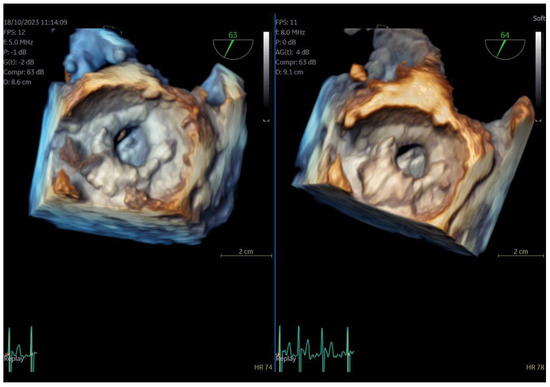

The adult probe was initially inserted for complete 2D/4D image acquisition, followed by the insertion of the pediatric probe while the patient remained under sedation. Remarkably, insertion of the pediatric probe was effortless in all cases, requiring no additional sedation. Despite encountering challenging diagnostic scenarios in all three cases (1st patient: combined severe aortic stenosis and severe mitral regurgitation (MR) due to P1 scallop prolapse, 2nd patient: malfunction of metallic mitral valve prosthesis with an occluded disk, 3rd patient: bioprosthetic aortic valve with paravalvular leak and significant MR in previously MV repair with a complete ring), the pediatric probe consistently provided high-quality images comparable to those obtained with the standard adult probe (Figure 1 and Figure 2, video S4). Notably, there was no compromise in 2D and 4D spatial and temporal resolution, with only minor differences observed compared to the adult 6VT-D probe (Table 1). Evaluation using the 5-point scoring system consistently yielded an average score close to 5 for all three cases, indicating excellent image quality (Table 1).

Figure 2.

Direct comparison of 3D volume-rendered “en face” images of a metallic prosthetic mitral valve with occluded disk. Left image corresponds to 6VT−D adult probe and right image corresponds to 9VT−D pediatric probe. Images enhanced with “photorealistic method” with Flexilight application (GE Healthcare).